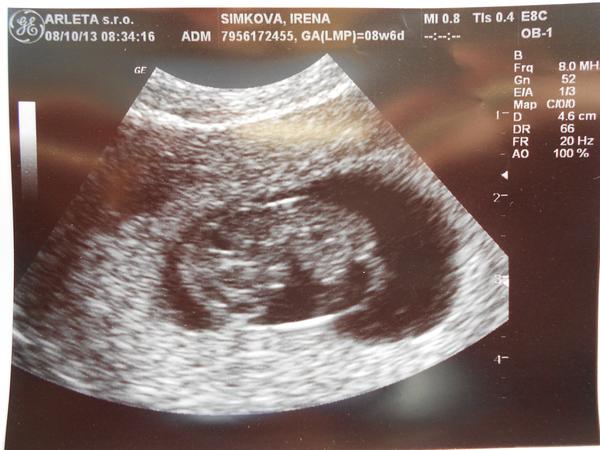

@megie4 hurááá, další krásný obrázek 🙂 moc blahopřeji !!!